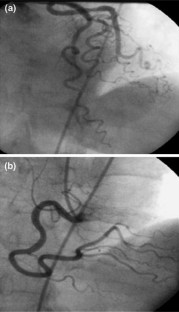

One hundred and four subjects who underwent coronary angiography were included in the study. Left anterior descending, left circumflex, and right coronary arteries were traced. Tortuosity was identified by the finding of ≥3 bends (defined as ≥45° change in vessel direction) along main trunk of at least one artery. Study population were divided into tortuosity (n = 54) and no tortuosity (n = 50) groups. Subjects were all submitted to pulsed-wave Doppler and two-dimensional echocardiographic examination to assess left ventricular functions.

Fig. 1